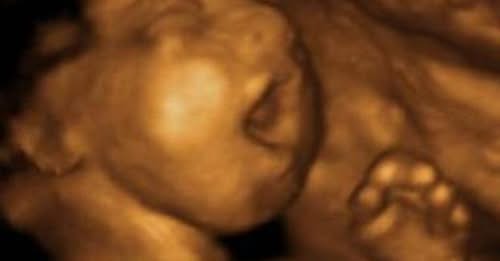

Wyoming Governor Mark Gordon signed a “fetal heartbeat” law that protects unborn babies by banning abortion in the state at about six weeks of pregnancy, which is before many women even know they are pregnant. The law makes Wyoming the fifth state to protect unborn babies at six weeks gestational age.

The “Human Heartbeat Act” bans abortions after a heartbeat can be detected. However, it does include exceptions for medical emergencies when the mother’s life is in danger, or her health is at risk of serious impairment. The law does not include exceptions for rape or incest.

“The state has a compelling interest in protecting the life of unborn members of the human race who cannot protect themselves,” reads the law. The act states that “medical evidence shows” a fetal heartbeat is a “key indicator that an unborn child is alive and will reach live birth.” Therefore, the law notes, it is an obligation of the state and its people to “support and encourage childbirth” to protect the state’s “future population” and “future stability.”